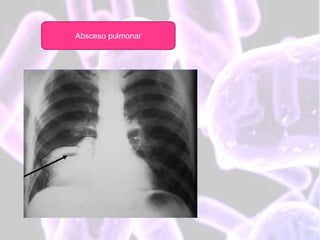

• EN LA RADIOGRAFÍA DE TÓRAX SE OBSERVA NIVEL HIDROAÉREO, CON IMAGEN

REDONDEADA, DE PAREDES GRUESAS.

Radiografía de Tórax (AP, lateral, oblicua)

 Típicamente la cavidad es de paredes

gruesas e irregulares, rodeado de infiltrado

pulmonar.